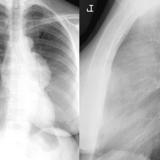

Case 8a Thymoma PA

Case 8b Thymoma Lat